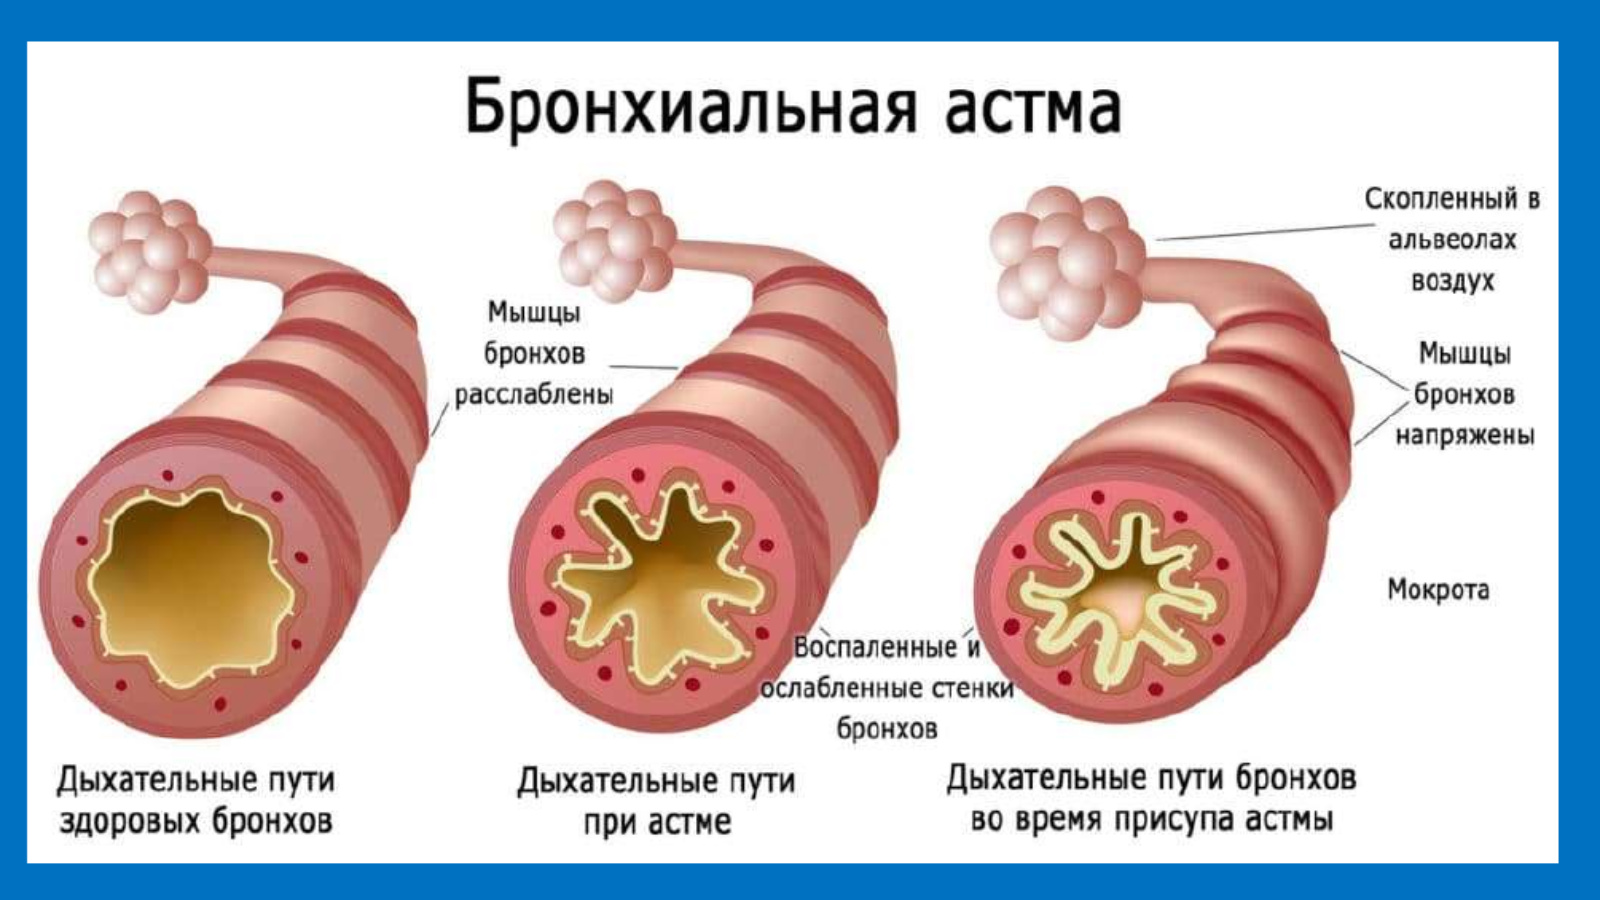

Медицинская тема: легочные осложнения при пневмонии